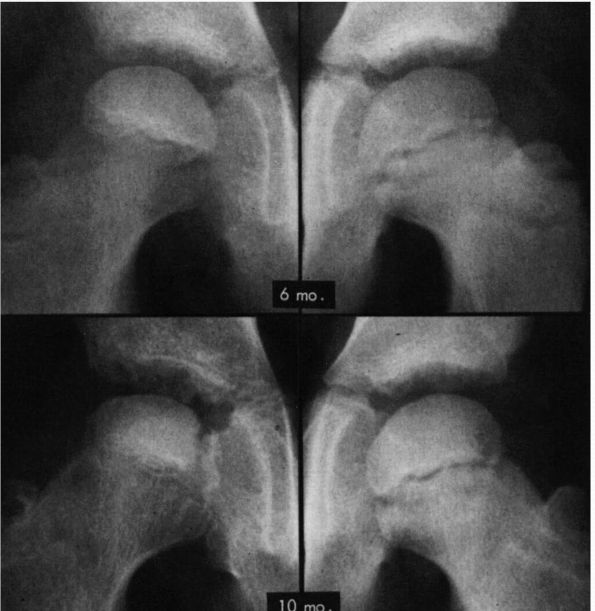

initial stage, the earliest radiographic signs of LCPD are failure of

the ossific nucleus to grow compared with the unaffected hip and

widening of the medial joint space caused by hypertrophy of the

articular cartilage of the femoral head (Figure 15-15).

The physician may also see a relative increase in radiodensity of the

femoral ossific nucleus in relation to the femoral neck. Radiolucencies

may be present in the metaphysis with thinning and irregularity of

the physeal plate (Figures 15-16 and 15-17).

A subchondral radiolucent zone (crescent sign) may also be present.

This radiolucent zone generally corresponds to the extent of the

necrotic portion of the ossific nucleus (Figure 15-18).

![]() |

|

FIGURE 15-15.

AP radiographs of the hip in a patient who developed Legg-Calvé-Perthes disease. On the initial film taken 6 months after onset of symptoms, the right ossific nucleus is smaller than the left, and the medial joint space is widened. Note also the retained density of the ossific nucleus compared with that of the normal hip and the relative osteopenia of the viable bone of the proximal femur and pelvis. Ten months after onset of symptoms, the evolution of the radiographic changes is seen. (Weinstein SL. Legg-Calvé-Perthes disease. Instr Course Lect 1983;32:272) |